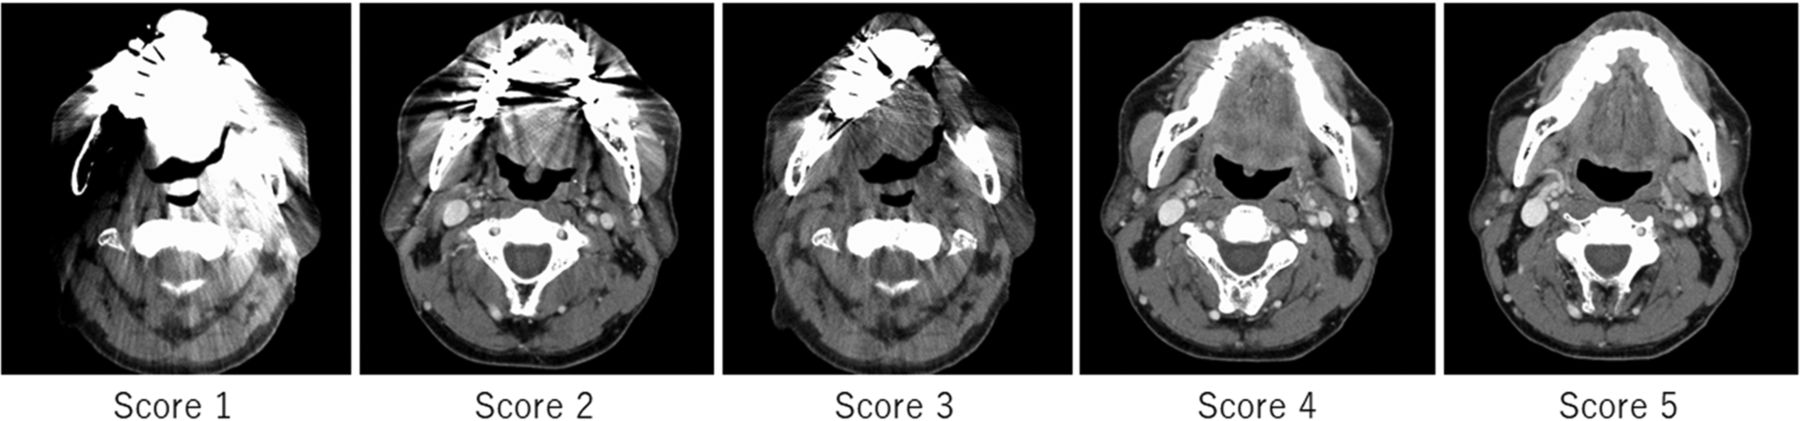

The readers evaluated the image-quality scores of metal artifact reduction and the depictions of representative structures (apex and base of the tongue, parapharyngeal space, superior portion of the internal jugular chain, parotid gland) on a 5-point scale (5, no artifacts/excellent visualization; 4, minimal artifacts/good visualization; 3, moderate metal artifacts/acceptable visualization for diagnosis; 2, severe metal artifacts in a small area/poor visualization; and 1, severe metal artifacts in a large area/no visualization), as shown in Fig 1. Finally, the readers assigned a diagnostic tumor stage according to the criteria of the American Joint Committee on Cancer, Cancer Staging Manual, 8th edition33 and examined the correlation between the qualitative metal artifact reduction score and the number of dental fillings or implants in each patient.

Representative CT images of the degree of metal artifact reduction. The image quality of metal artifact reduction was scored using the following 5-point scale: 1, severe metal artifacts in a large area; 2, severe metals artifact in a small area; 3, moderate metal artifacts; 4, minimal metal artifacts; and 5, no metal artifacts.